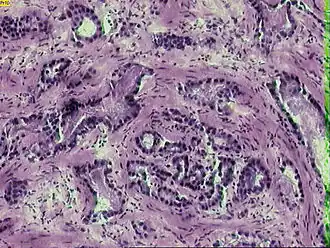

Микрофотография инвазивной аденокарциномы простаты